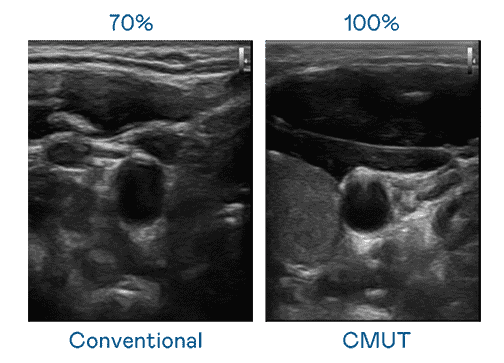

CMUT 技术是一种用电容式微机电元件来产生超音波讯号的技术。。。。与传统 PZT 压电式技术相比,,CMUT 频宽增加 30%,,,更宽频的超音波讯号让影像解析度大幅提升,,,,是实现高影像品质医疗超音波扫描、、、、促进精准医疗发展的关键技术。。。。

超音波影像的解析度高低,,首先取决于探头能发出的讯号频宽。。。壹号平台 CMUT 可提供高清晰的超音波讯号,,,,提供高频宽、、、高灵敏度、、、影像纹理细节更高的超音波影像,,协助医护人员缩短影像判读时间及利用精准的医疗影像进行诊断。。。